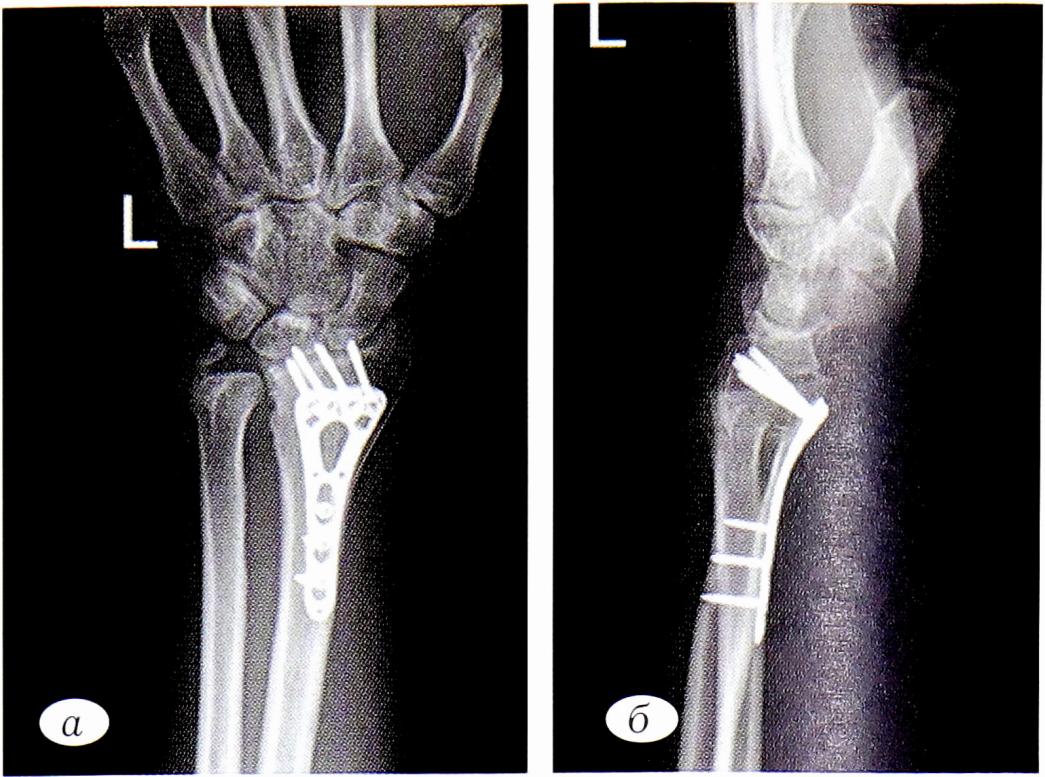

В тот же день были выполнены установка дистракционного аппарата Коршунова—Лазарева (рис. 1, а, б), остеосинтез левого бедра интрамедуллярным стержнем. Спустя 6 сут после стабилизации состояния пациента была выполнена операция — конверсия дистракционного аппарата, накостный остеосинтез пластиной LCP-VA («Synthes») (см. рис. 1, в, г).

Рис. 1. Рентгенограммы левого предплечья пациента П. а — внутрисуставной оскольчатый перелом дистального метаэпифиза лучевой кости, перелом шиловидного отростка локтевой кости. После установки дистракционного аппарата Коршунова—Лазарева (прямая проекция); б — боковая проекция (смещение отломков в аксиальной плоскости). Контрольные рентгенограммы левого предплечья после остеосинтеза пластиной через 6 сут: в — прямая проекция; г — боковая проекция.

Fig. 1. X-rays of patient P.’s left forearm. a — intra-articular comminuted fracture of the distal lUBtipifica of the radius, fracture of the styloid process; ulna. After installation of the distraction apparatus Korshunov— Lazarev (direct projection); b — side projection (displacement of fragments in the axial plane); c — controlling x-rays of the left forearm after oleosinBtesa plate after 6 days: in direct projection; d — BokofflWai projection.

Рис. 2. Контрольные рентгенограммы спустя 12 мес с момента выполнения оперативного лечения. а — прямая проекция; б — боковая проекция.

Fig. 2. Control radiographs after 12 months from the moment of surgical treatment. a — direct projection; b — lateral projection.